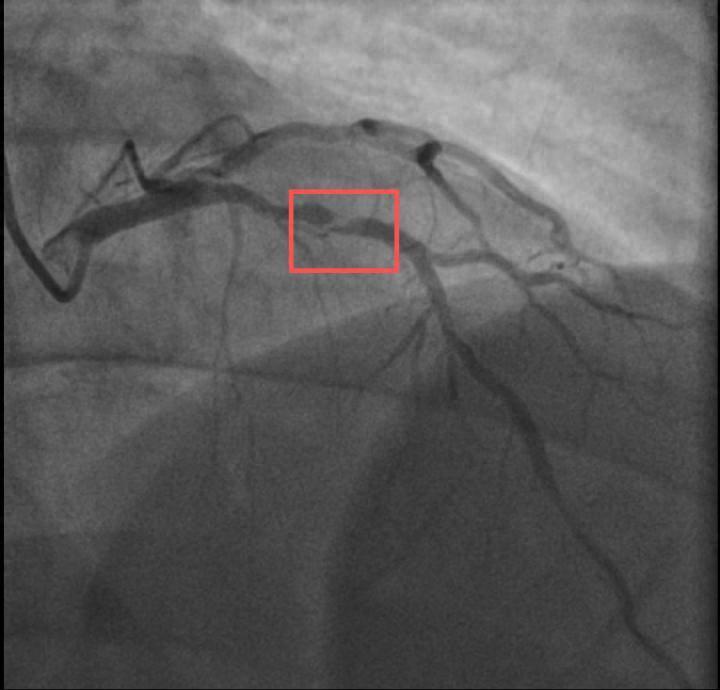

介入诊疗前影像图

浙江病院心血管内科的医师疏析,剧烈畅通导致这位患者腹黑的不融会斑块破碎,进而酿成前降支近段次全阻滞。所幸送医实时,孙先生的体魄险情被化解。

介入诊疗后影像图